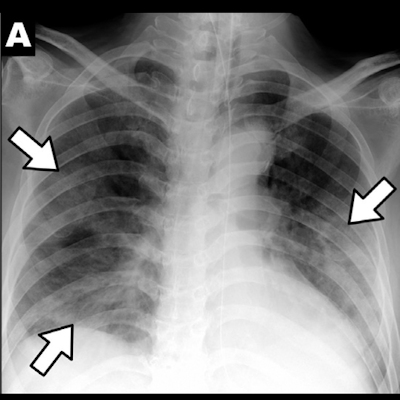

Available within QUIBIM's Precision image analysis platform, the artificial intelligence (AI)-based Chest X-Ray Classification tool is designed to help radiologists prioritize interpretation of radiographs that are potentially pathological, according to the company. The software is based on "referee" networks and convolutional neural networks that have been trained with a database of more than 500,000 images. After calculating the final probability of a chest x-ray being abnormal, the tool then utilizes these probabilities to estimate the presence of pathologies, QUIBIM said.